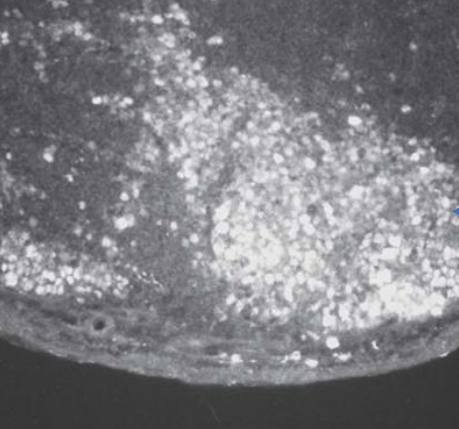

『乳酸菌生成エキス』の摂取による老齢マウス(58週齢)の<パイエル板>にいる免疫細胞の変化

中心部に加齢による退縮がみられる。

中心部が活性化している。